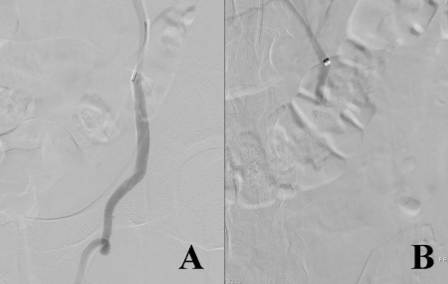

图片

术前(A)/ 术后(B)